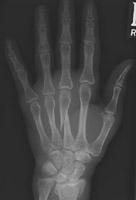

- Click on the image for a larger versionDPA radiograph of a fracture of the second metacarpal.